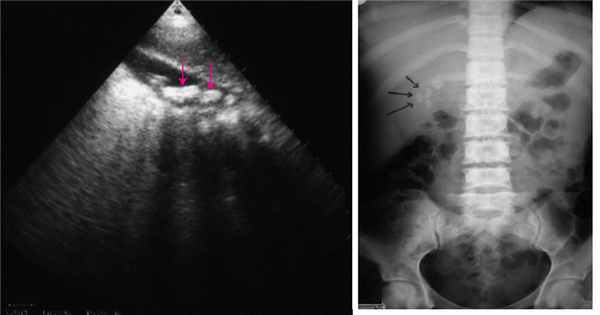

Чреспеченочная холангиостомия при нерасширенных желчных протоках

Цель. Повышение эффективности рентгенхирургического лечения послеоперационных осложнений (наружные желчные и дуоденальные свищи, абдоминальные скопления желчи).

Материал и методы. Чрескожная чреспеченочная холангиостомия при нерасширенных желчных протоках выполнена 11 пациентам. Необходимость наружного желчеотведения была обусловлена несостоятельностью культи двенадцатиперстной кишки у 5 пациентов после резекционных вмешательств на желудке, наличием наружного желчного свища после хирургического вмешательства на желчном пузыре и внепеченочных желчных протоках у 3 пациентов и тяжелым панкреонекрозом в 3 наблюдениях. Результаты. Наружное желчеотведение позволило устранить дуоденальные свищи консервативно у 5 пациен-

тов, желчные свищи у 3 пациентов с ятрогенным повреждением общего желчного протока. В 3 наблюдениях холангиостомический дренаж осуществлял наружное желчеотведение у пациентов с тяжелым панкреонекрозом. Два осложнения антеградной холангиостомии – подкапсульная гематома печени и портобилиарная фистула были эффективно ликвидированы миниинвазивными методами: выполнено чрескожное дренирование гематомы и разобщение портобилиарной фистулы пломбировкой внутрипеченочного канала.

Заключение. Антеградная холангиостомия в условиях нерасширенных желчных протоков отличается от традиционной, зачастую предполагает предварительное контрастирование желчных протоков любым доступным способом и требует строгого соблюдения технологии